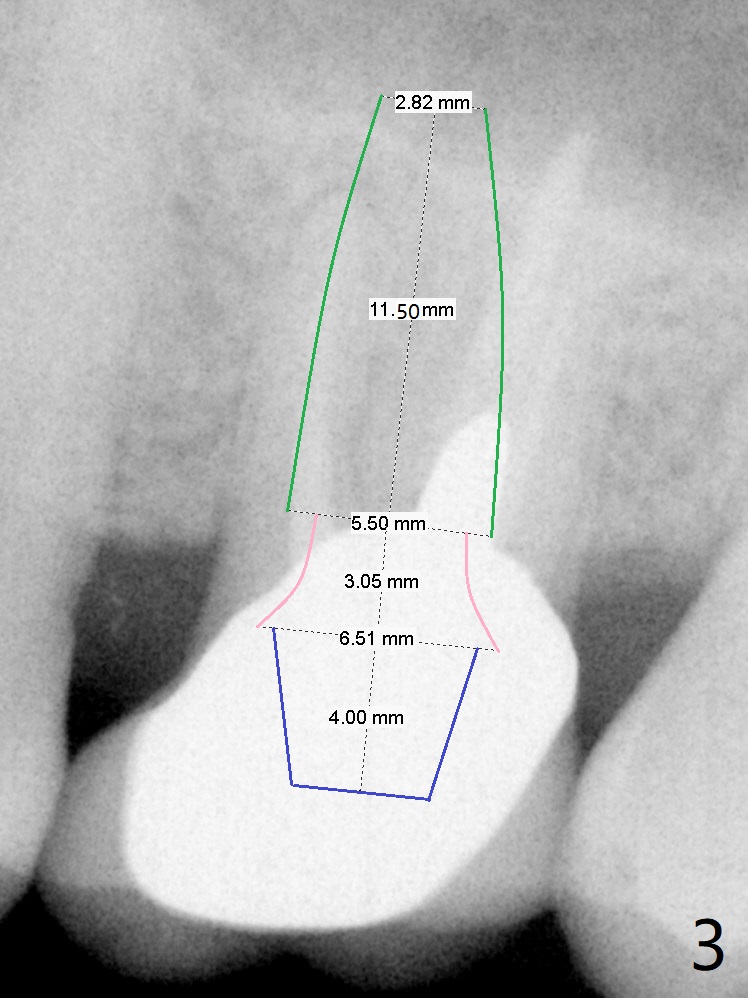

A 64-year-old man will return for #14 extraction/implant due to palatal root fracture (Fig.1,2). He has a history of cheek bite when the teeth #1-3 are replaced by implant crowns. His models for these crowns have been found. Alginate impression has been taken for the arches so that the new crown will be fabricated as close as possible to his original one. Take preop photos to show palatal root fracture and overjet buccally. Initiate osteotomy in the septum slightly buccally due to the palatal bone defect; the depth will be 8.5 mm (Fig.1,2). Use DIO Bone Expanders or an implant to break the sinus floor (Fig.3). The implant will be placed slightly apical to the crest.